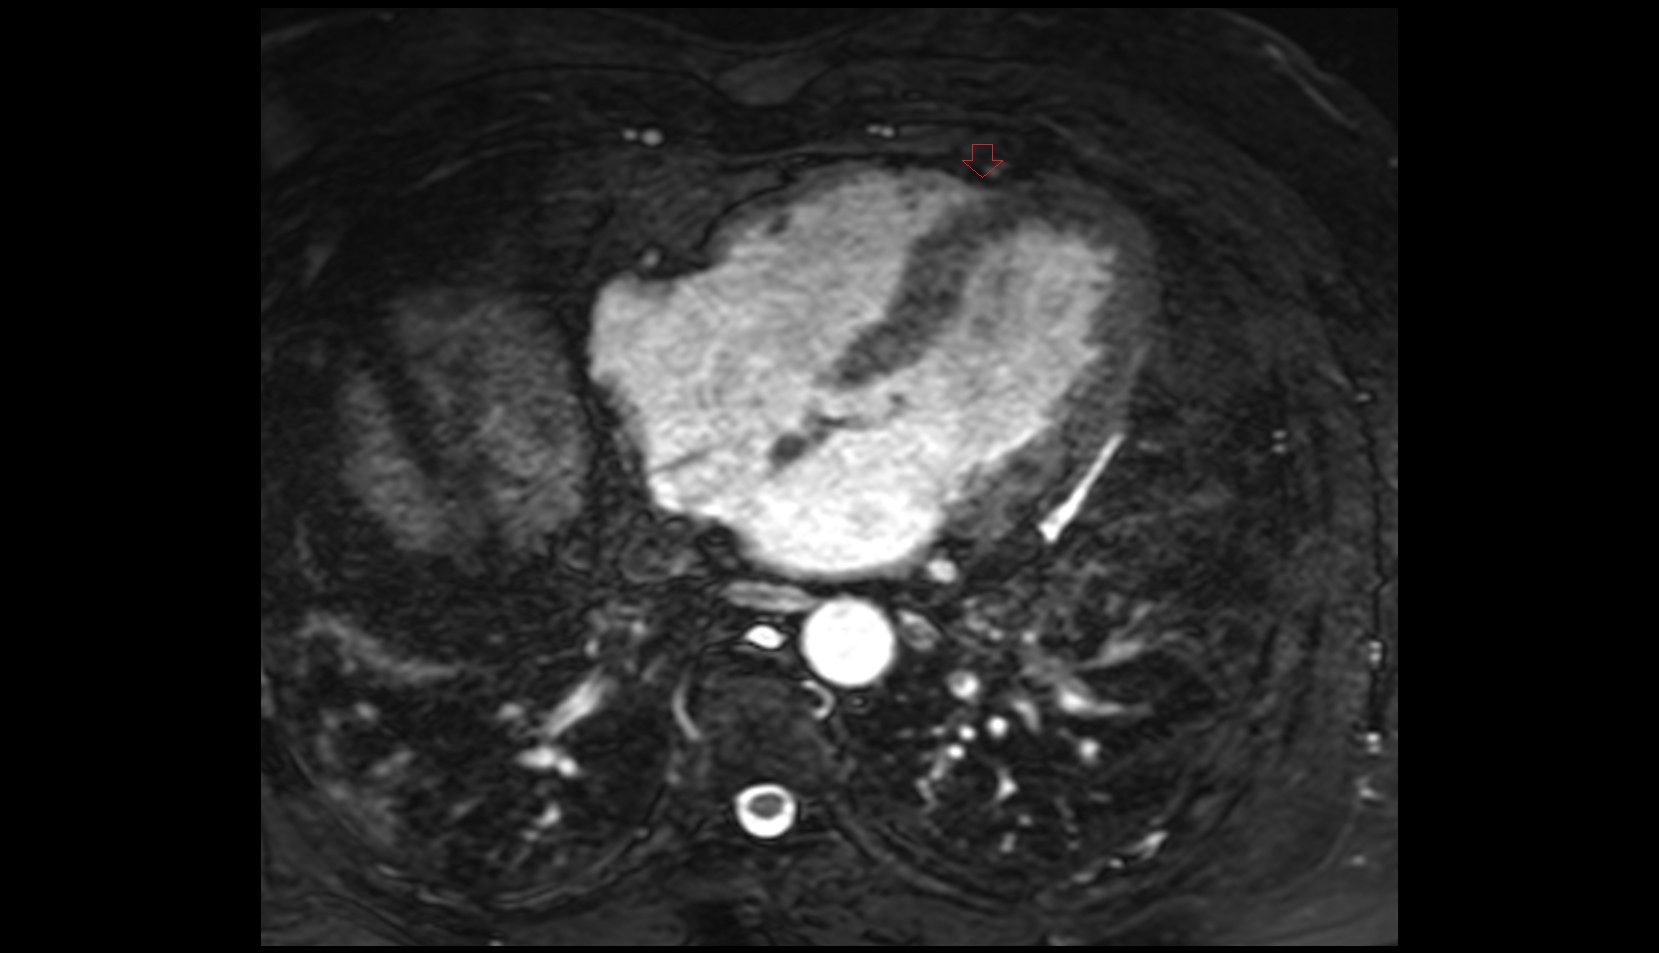

- Left anterior descending artery (LAD)

- Circumflex artery (LCx)

- Left main coronary artery (LMCA)

- Right coronary artery (RCA)